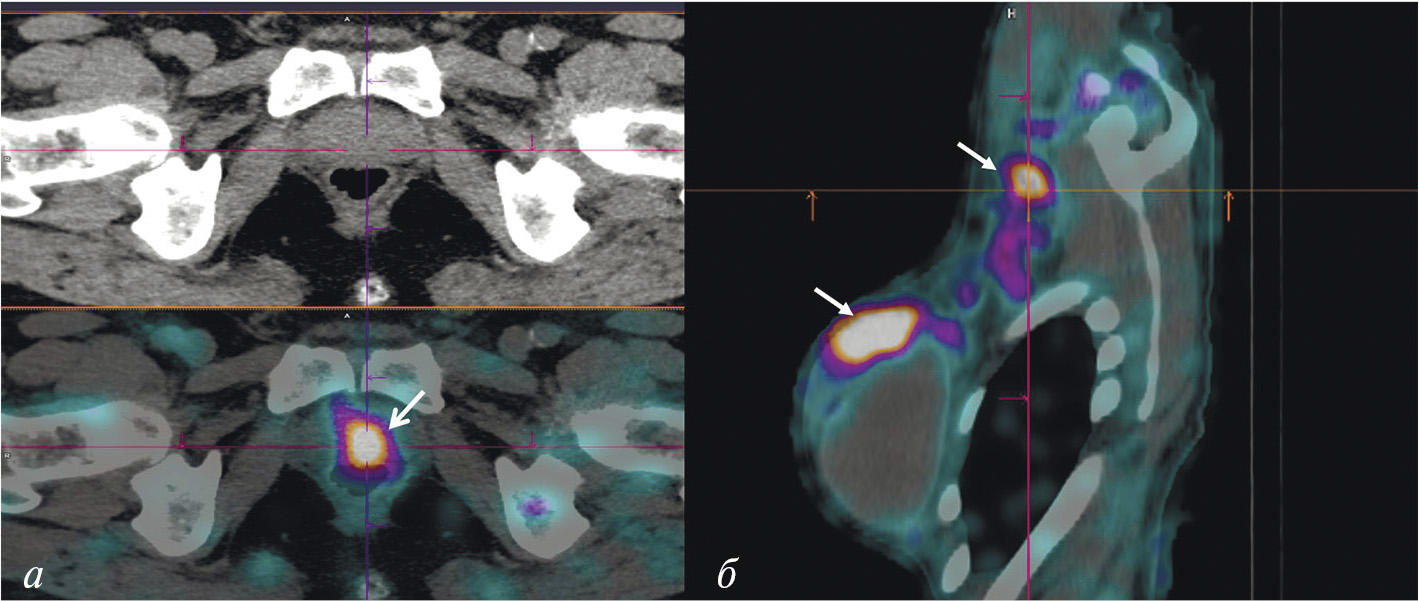

Имеющиеся в арсенале радиологов радиофармацевтические лекарственные препараты для визуализации СЛУ отличаются невысокой аккумуляцией (1.5–2% от введённой дозы). Поэтому в НИИ онкологии Томского НИМЦ и ТПУ был разработан оригинальный РФЛП на основе гамма-оксида алюминия “Сентискан, 99mТс” с высокими (около 12% от введённой дозы РФЛП) уровнем накопления в сторожевых лимфатических узлах [46]. Набор для его приготовления получил регистрационное удостоверение. Клинические испытания показали оптимальную фармакокинетику этого индикатора для интраоперационного выявления СЛУ и высокую эффективность при хирургических вмешательствах в случае рака шейки матки, рака эндометрия и злокачественных новообразований молочных желёз (рис. 9) [47, 48].

Рис. 9. ОФЭКТ/КТ пациентки с раком правой молочной железы после паратуморального введения РФЛП “Сентискан, 99mТс”